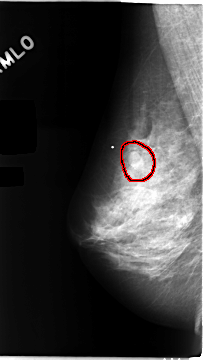

C_0104_1.RIGHT_MLO

FILE: C_0104_1.RIGHT_MLO.OVERLAY

TOTAL_ABNORMALITIES 1

ABNORMALITY 1

LESION_TYPE MASS SHAPE OVAL MARGINS CIRCUMSCRIBED

ASSESSMENT 3

SUBTLETY 5

PATHOLOGY BENIGN

TOTAL_OUTLINES 1

BOUNDARY